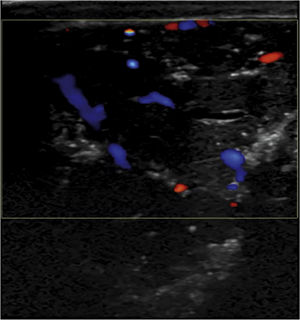

Paciente de 51 años con antecedentes de tabaquismo, consumo de cocaína, hipertensión arterial, infección por virus de la inmunodeficiencia humana, hemorragia subaracnoidea, tuberculosis pulmonar, hepatopatía crónica por virus C, psicosis con componente tóxico y adenocarcinoma de pulmón en estadio IV con metástasis óseas. Acudió a consulta por bultoma de 4 meses de evolución en región frontal izquierda de rápido crecimiento. En la exploración física se observó una tumoración blanda de 8×5cm, adherida a planos profundos, no dolorosa, sin signos inflamatorios, que se localizaba a nivel dérmico (fig. 1). La exploración neurológica fue normal. Se realizó ecografía en la misma visita, donde se observó una lesión redondeada, de 6cm de diámetro mayor, de ecogenicidad heterogénea, con múltiples calcificaciones puntiformes y vascularización central (fig. 2). Se inició tratamiento radioterápico antiálgico paliativo, pero la lesión continuó creciendo progresivamente y se produjo un importante deterioro del estado general, por lo que se decidió realizar tratamiento paliativo domiciliario.

Las metástasis cutáneas se producen por la infiltración de la piel por células malignas procedentes de una neoplasia primaria. Su diagnóstico es un reto en la práctica clínica debido a su variable presentación y su detección tardía, con el consiguiente impacto en el tratamiento y pronóstico del paciente. Tienen una incidencia del 0,7-9% y suelen aparecer en fases tardías de la enfermedad1. Los tumores que con mayor frecuencia presentan metástasis cutáneas son el cáncer de mama en las mujeres y el cáncer de pulmón en los hombres1,2. Los pacientes con cáncer de pulmón desarrollan metástasis en la piel en el 1-12% de los casos, siendo el adenocarcinoma el tipo histológico más frecuente1,3. Se presentan habitualmente como un nódulo indoloro, redondeado u ovalado, de textura firme y de rápido crecimiento. Con menor frecuencia se observan placas o tumoraciones, como en el caso descrito. Suelen localizarse en tórax, abdomen, cabeza, cuello o cuero cabelludo4,5 El diagnóstico se basa en la anamnesis y exploración cutánea minuciosa. Aunque el diagnóstico de confirmación requiere estudio histológico, la ecografía cutánea es una prueba de imagen con gran potencial para orientar el diagnóstico. Actualmente no existe un patrón ecográfico definido, pero las metástasis cutáneas suelen ser lesiones localizadas en la unión dermoepidérmica, hipo- o isoecogénicas, de contornos irregulares, heterogéneas y con vascularización aumentada en el modo Doppler color6. Cuando se detectan metástasis en la piel, suelen existir metástasis en otros órganos, como en nuestro paciente. En este contexto de enfermedad avanzada, la presencia de metástasis cutánea se asocia a mal pronóstico del cáncer de pulmón, con una supervivencia media de 5 meses4,5. En conclusión, aunque las metástasis cutáneas son una entidad rara en los pacientes con cáncer de pulmón, deben sospecharse ante la aparición de lesiones cutáneas de rápido crecimiento. La ecografía cutánea es una técnica rápida y segura que puede ayudar a su diagnóstico y seguimiento.